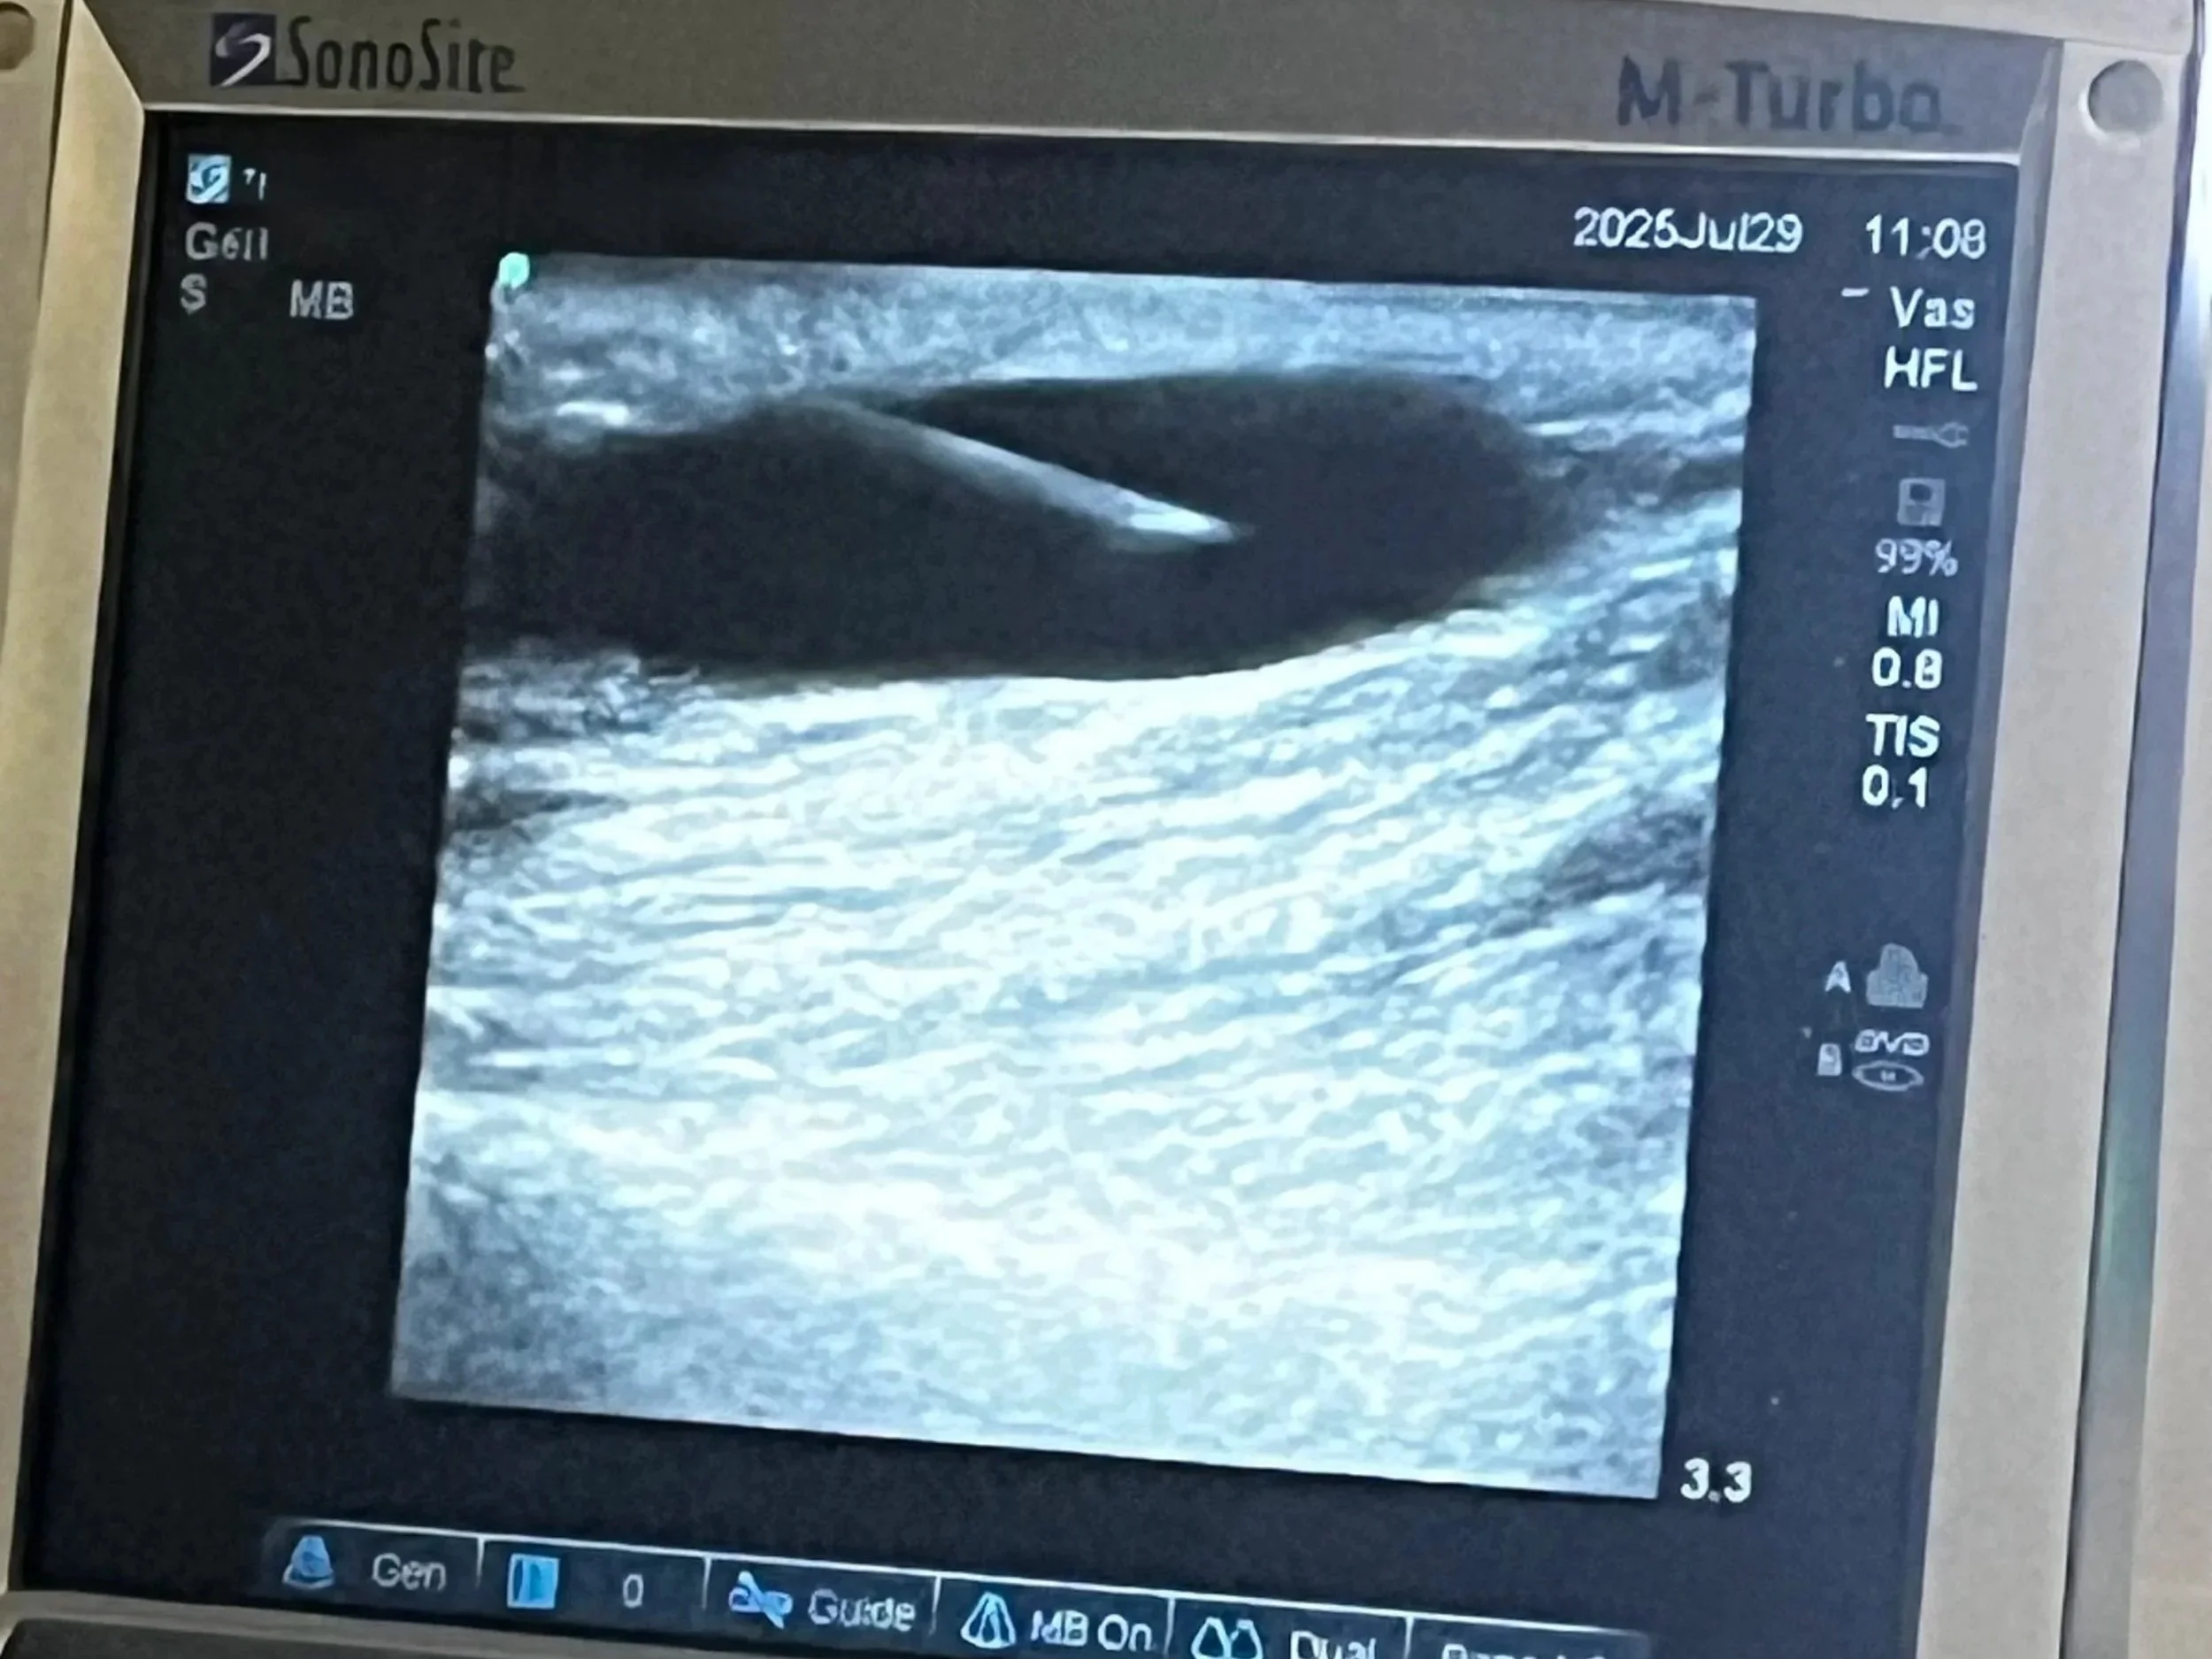

Needle being inserted using ultrasound guidance into patient's arm for dialysis.

• This is an image of an ultrasound machine being used to guide a dialysis nurse into inserting the needle in a complicated access. The black area is the vein, and the object inserted is the needle.